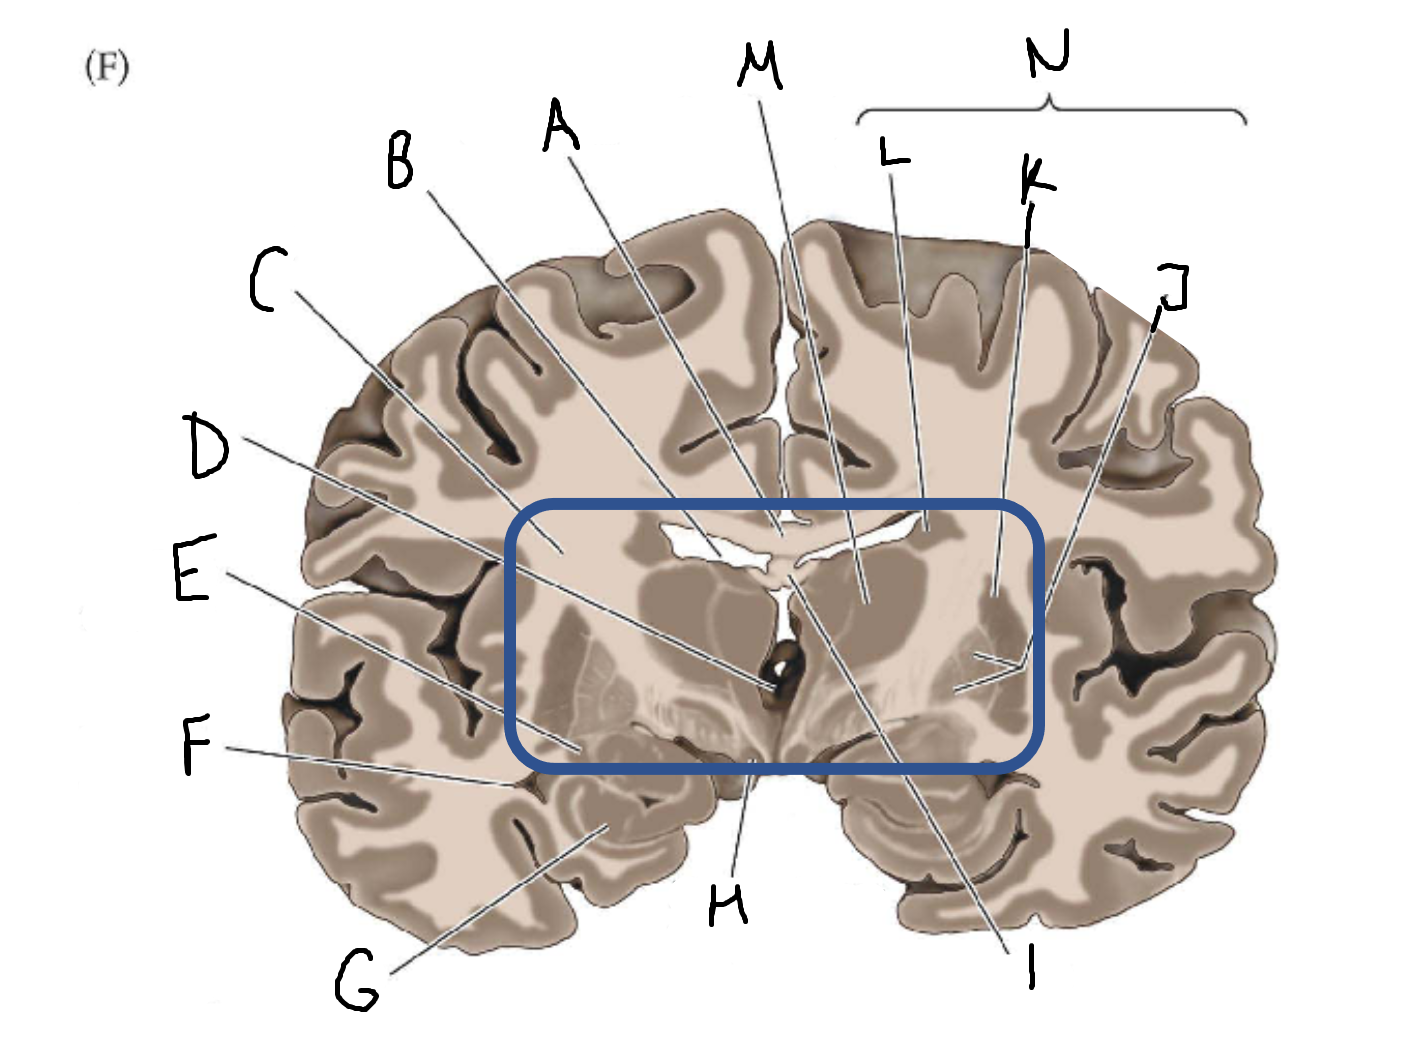

A

corpus callosum

B

lateral ventricle

C

internal capsule

D

third ventricle

E

tail of caudate nucleus

F

lateral ventricle

G

hippocampus

H

mammillary body

I

fornix

J

globus pallidus

K

putamen

L

caudate

M

thalamus

N

basal ganglia